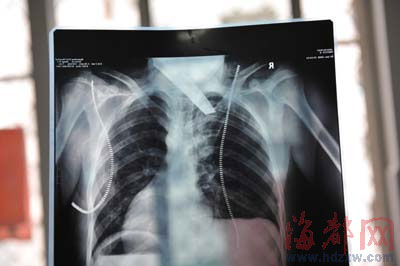

前晚,在第一醫院急救室,經過4個多小時的搶救,醫生將匕首從小勇身上取出,發現這把匕首的刀尖扎斷了1厘米。由于小勇肺部被刺中,昨天上午,醫生再次進行了3個多小時的手術,切除了受傷的部分肺,直到下午,小勇才挺過來。“挺了一夜,現在總算醒了過來。”楊女士一夜沒睡,守在手術室外7個多小時,生怕兒子再醒不過來。不過,由于傷勢嚴重,小勇目前戴著氧氣呼吸,仍未脫險。